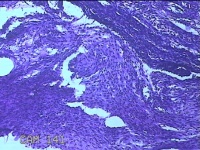

右侧卵巢囊肿

性别

女

年龄

临床诊断

一般病史

下腹痛3天。

标本名称

大体所见

灰白暗红色囊壁样组织2.5x1.5x0.3cm一块,表面糜烂,因已切开,囊内容物已流失,囊壁厚0.1cm。

图3